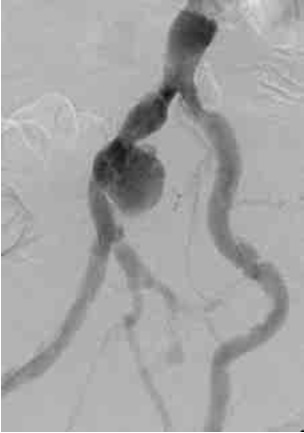

![]() |

| Figure 2: Various locations of iliac artery aneurysms and stent placements |

- Isolated iliac artery aneurysms are rare (Figure 2). Isolated internal iliac artery aneurysms are embolized. Pre-procedural embolization of internal iliac artery may also be necessary to prevents retrograde filling of the aneurysmal sac and late rupture. In case of aneurysm of distal part of external iliac artery contralateral access is gained and followed by a cross-over technique. This is done because the femoral access site will either be too close or may itself be part of the aneurysm. Same access applies for sub-intimal dissections and iliac occlusive disease in distal part of the external iliac artery. Majority of iliac aneurysms are accompanied with infra-renal aortic aneurysms that need to be treated concomitantly. Similarly, common iliac artery and proximal external iliac without proximal neck necessitates stent graft placement in the aortic bifurcation (Figure 3).